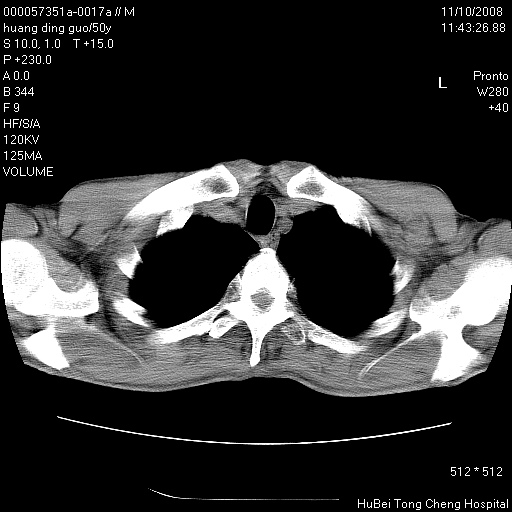

患者 男,50岁。左侧腰背部疼痛3月余,伴消瘦。平素健康,无传染病史。

胸部ct轴位平扫(层厚10mm,螺距1.5,重建间隔10mm),图像如下:

左肺下叶背段有一厚壁空洞,外壁呈锯齿状伴毛刺改变。空洞相邻胸膜有牵拉改变。左肺下叶血管支气管束不规则增粗,小叶间隔增厚。胸椎骨质破坏。考虑左肺下叶周围型肺癌伴左肺下叶癌性淋巴管炎、胸椎转移。

左肺下叶背段有一厚壁空洞,外壁呈锯齿状伴毛刺改变。空洞相邻胸膜有牵拉改变。左肺下叶血管支气管束不规则增粗,小叶间隔增厚。胸椎骨质破坏。考虑左肺下叶周围型肺癌伴阻塞性肺炎、胸椎转移。其他待排

左肺下叶背段有一厚壁空洞,内壁不规则,外壁呈锯齿状伴毛刺改变。空洞相邻胸膜有牵拉改变。周围呈絮状炎性改变,左肺下叶血管支气管束不规则增粗,小叶间隔增厚。胸椎骨质破坏。考虑左肺下叶周围型肺癌伴左肺下叶阻塞性肺炎、胸椎转移。